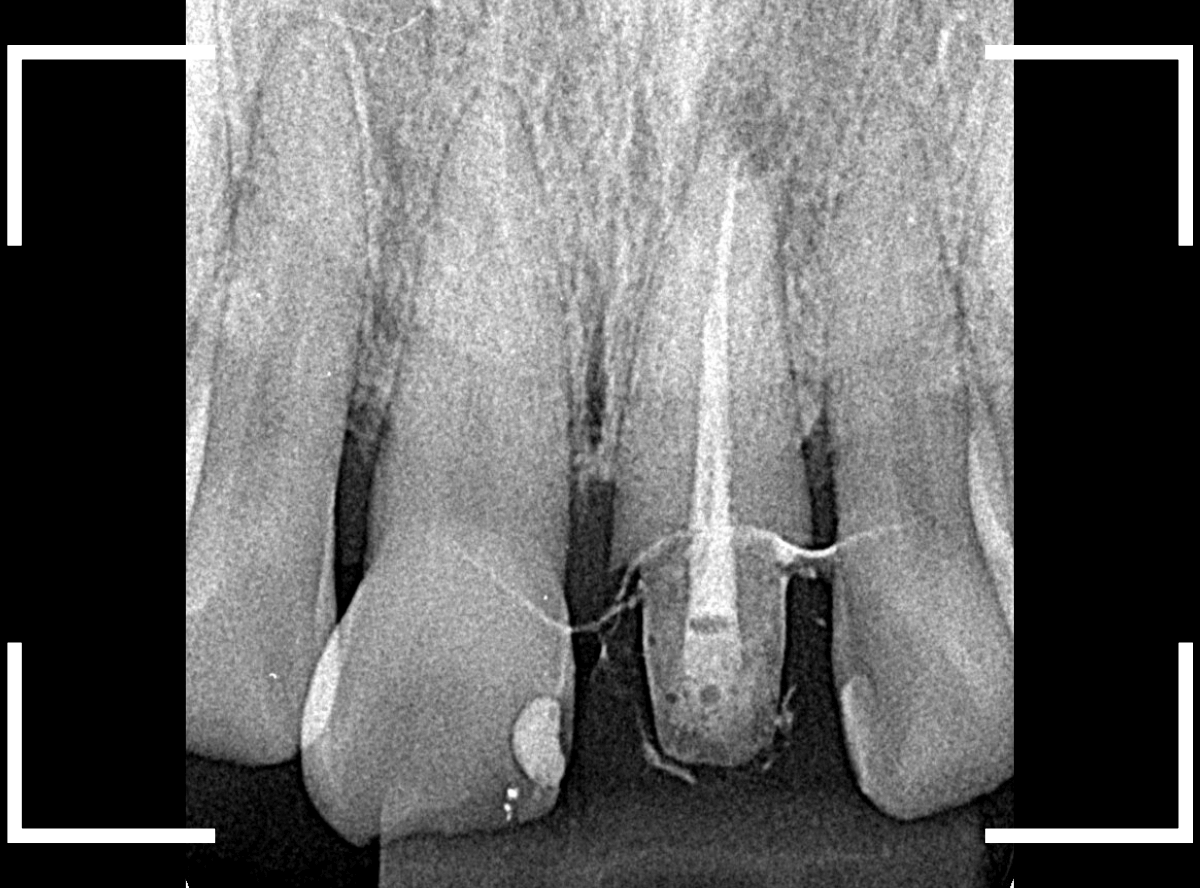

まず、歯周病の治療と並行して、神経の治療を行います。

さし歯を被せるために、歯の土台をたてて、歯を削ります。

歯の高さが低く、このままさし歯を作っても、すぐに取れてしまう事が予想されます。

隣りの歯と比べても歯肉の際が浅いため、若干歯肉を切開して、歯の高さを稼ぎます。

歯肉を切開した部分に、仮歯のレジンを盛って確認します。

大体、隣の歯の高さと合わせる事が出来ました。

しばらく経過観察して、歯肉が落ち着いたところです。

さし歯を入れるのに心配ない程度の歯の高さが確保でき、さし歯を作るための準備が整いました。

今回は、審美性と、清掃性が高く、歯周病が進行しにくいという利点を考慮して、ジルコニア・セラミックでの治療を選択されました。

ジルコニア・セラミックset後の状態です。

仮歯で細かく調整したおかげで、下の歯のかみ合わせは若干の調整で済む事ができました。